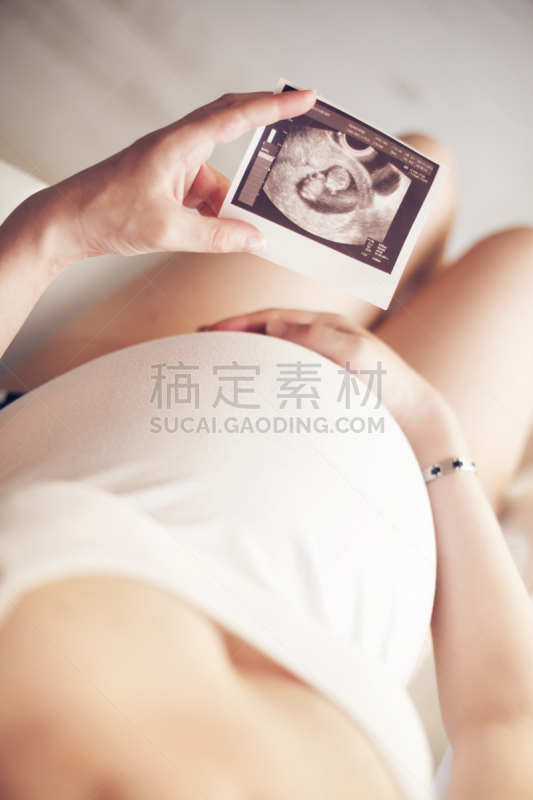

孕妇和超声波扫描详情

JPG